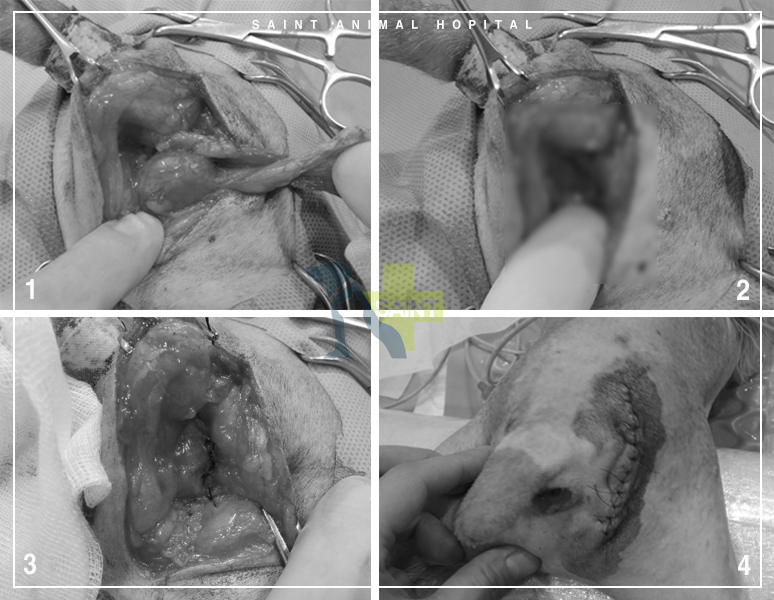

피부를 절개해 탈장한 부위를 노출시키자 탈장한 조직은 예상치 못한 방광이었습니다.초음파로 방광경부가 제대로 확인되지 않은 탈장으로 인한 문제라는 것도 알았습니다.

방광을 환납하고 주변 조직을 정리했습니다.그리고 탈장한 부위를 재탈장하지 않도록 꼼꼼히 봉합했습니다.